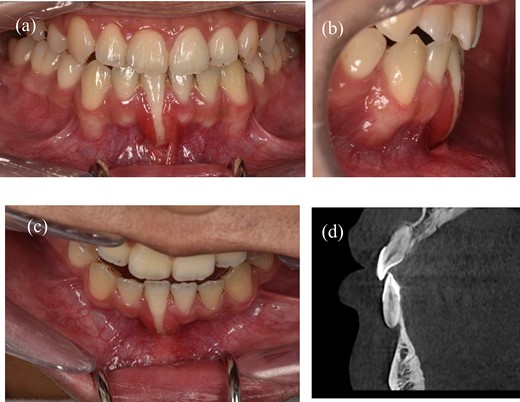

A 22-year-old male patient exhibited an isolated buccal recession of Class I Cairo [5] on tooth 41, showing indications of significant inflammation in the marginal soft tissue. The patient had received a comprehensive orthodontic treatment 2 years ago. During the initial examination, there was a fixed lingual retainer extending from tooth 34 to tooth 44. The patient initially reported no recession of 41 after orthodontic treatment, but one year later, the recession appeared and became more serious after that. A fixed retainer can cause side effects on the teeth if it is not passive, leading to an undesirable force system and moment in the labial-lingual side (Fig. 1b) where the torque of tooth 41 showed a significant difference compared to other teeth. The periodontal assessment indicated the presence of a thin gingival phenotype, and a marginal tissue recession that exhibited a depth of ~9 mm, a width of 3 mm, and attached gingiva was absent. The measurement of marginal tissue recession was noted as the distance from the cemento- enamel junction to the tissue margin (Fig. 1a–c). Panoramic and cone beam computed tomography assessments were conducted. In the sagittal cross-sectional view of the cone beam computed tomography (CBCT) scan, the tooth exhibited malpositioning, extending beyond the dental alveolar bone (Fig. 1d).

A 22-year-old man exhibits gingival recession in the lower left central incisor. (a) Intraoral image illustrating the labial view. (b) Intraoral image illustrating the lateral view. (c) Intraoral image illustrating the bird’s-eye dental view. (d) CBCT radiograph capturing the recession region.